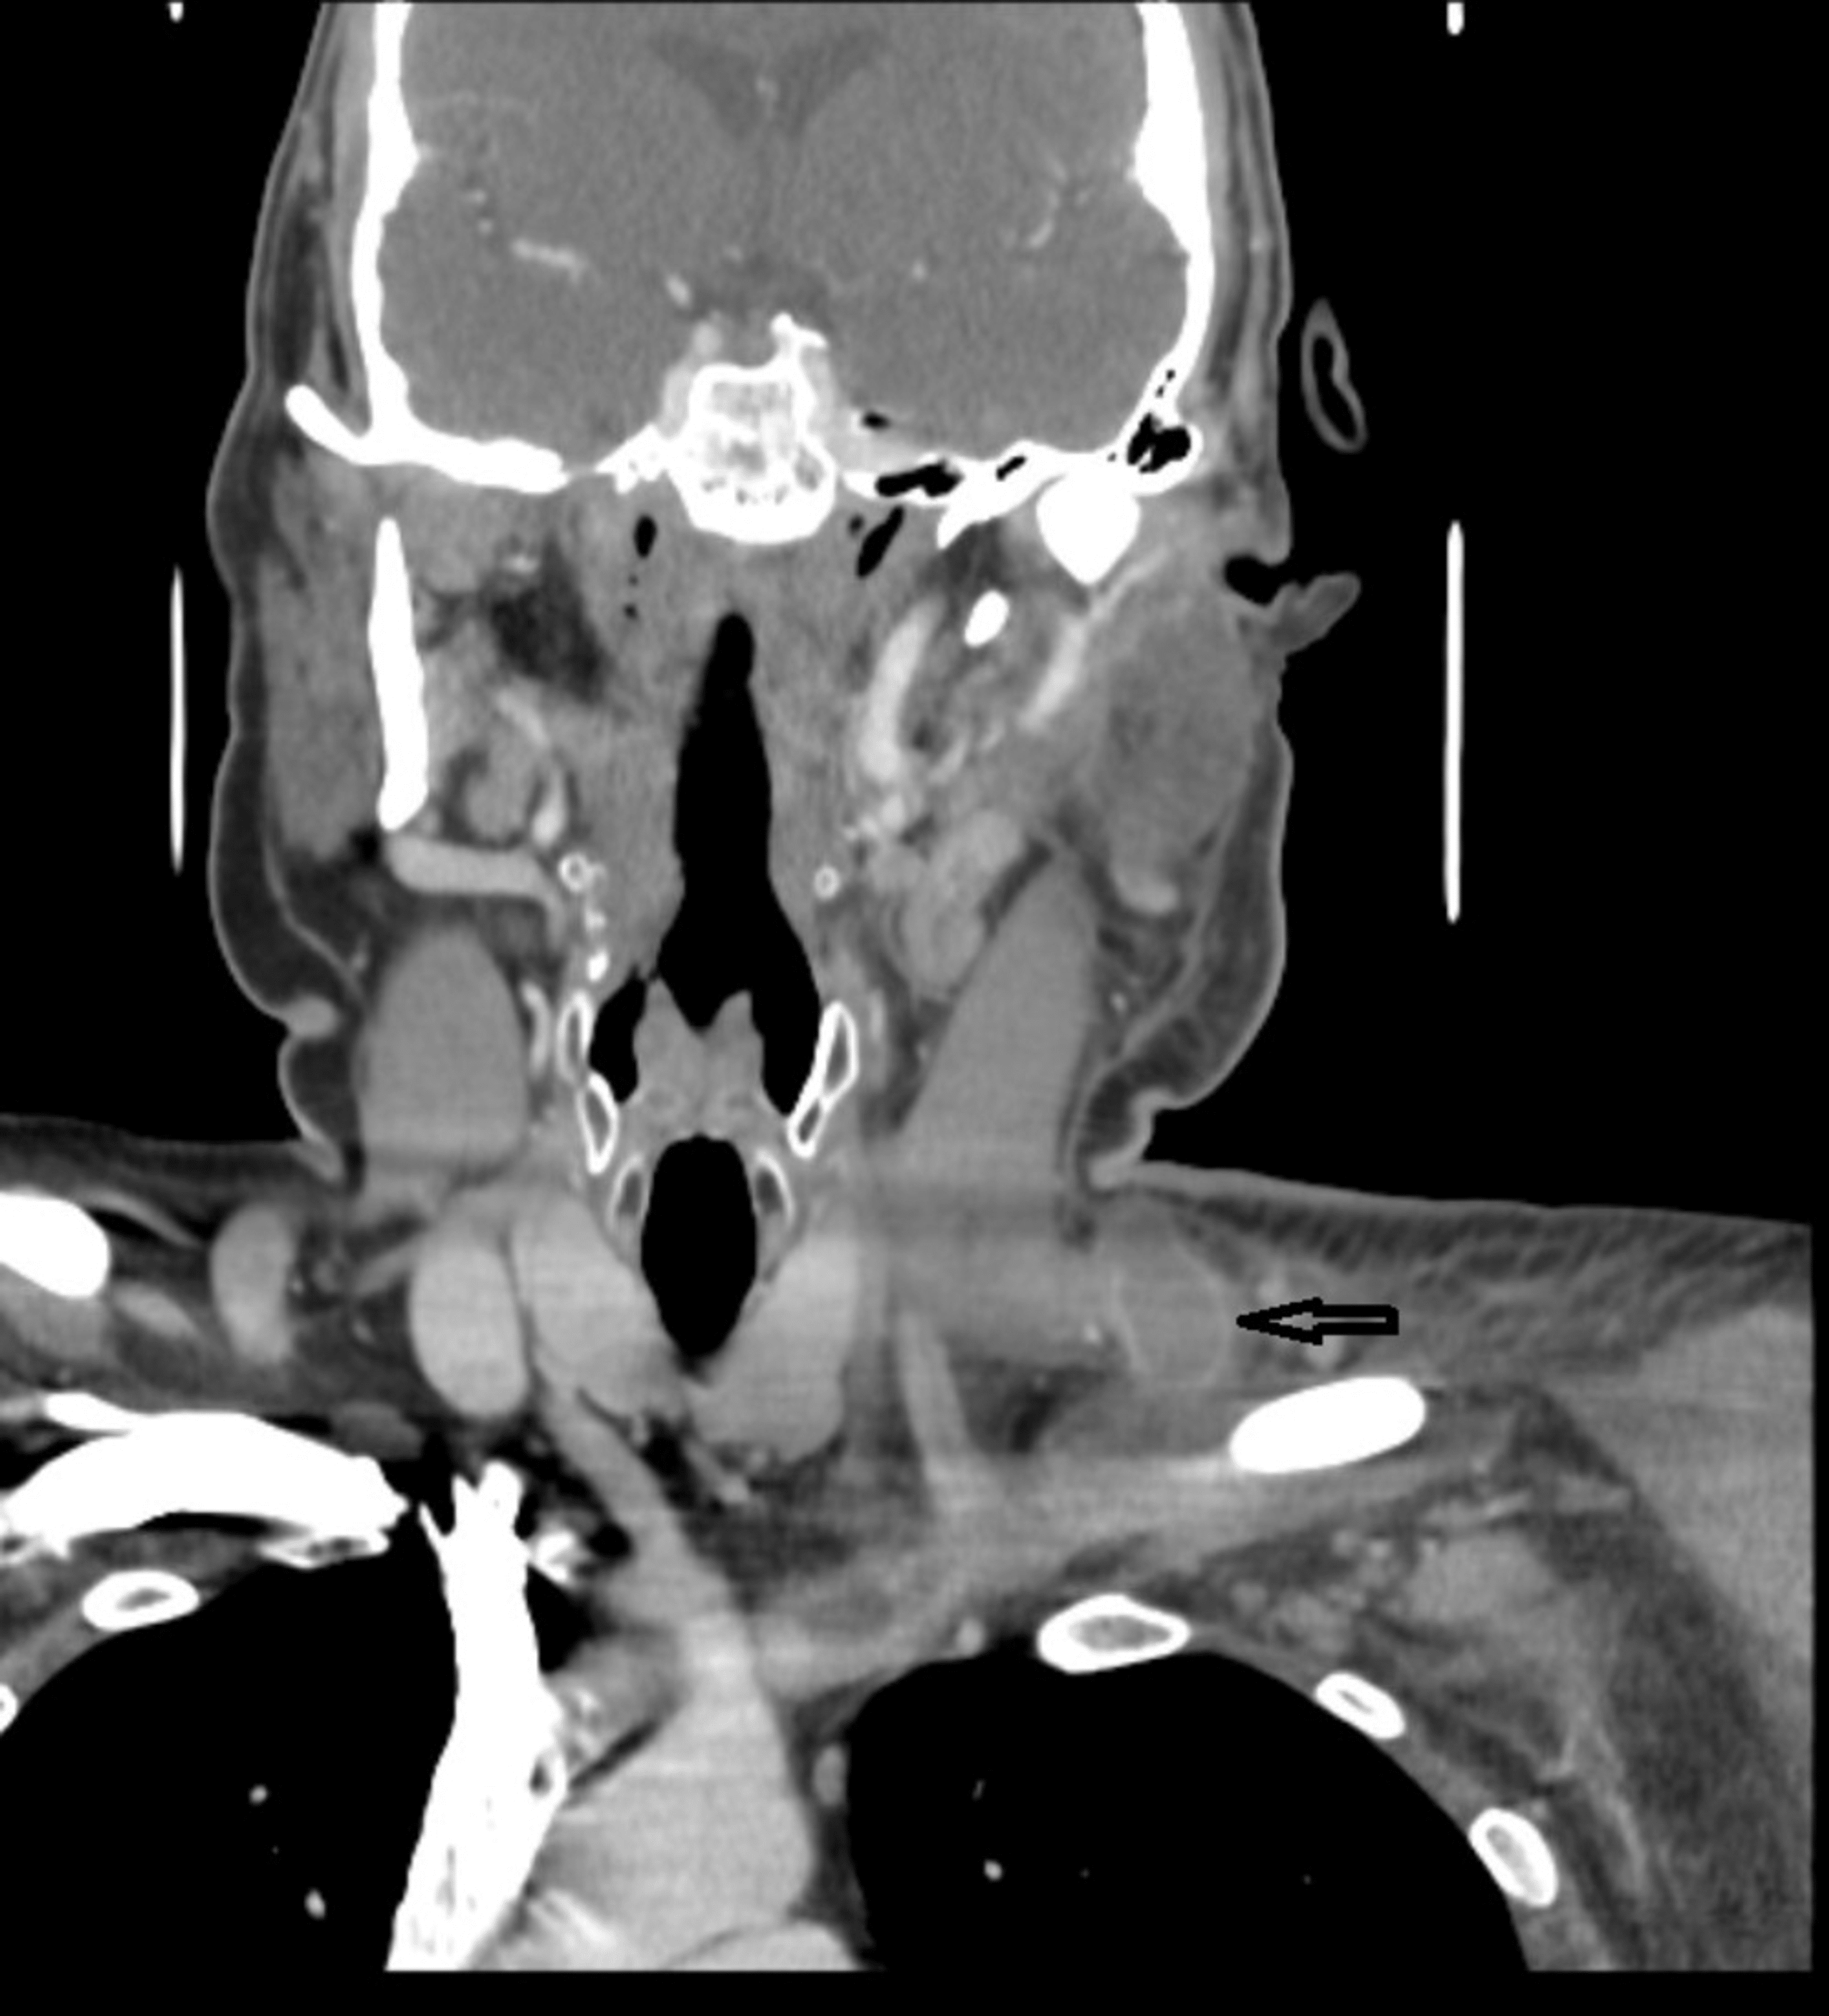

External jugular vein thrombosis secondary to deep tissue neck massage

CTA of the neck revealing thrombosis of the right IJV (arrow); (A Tumor On Jugular Vein In Neck ijv thrombosis is the formation of thrombus located intraluminally in the ijv. tumors that grow in this area are called glomus jugulare tumors because they form at the top of the jugular vein. jugular bulb (glomus jugulare) — glomus tumors are most common in this region of the jugular vein just below the middle ear. jugular. Tumor On Jugular Vein In Neck.